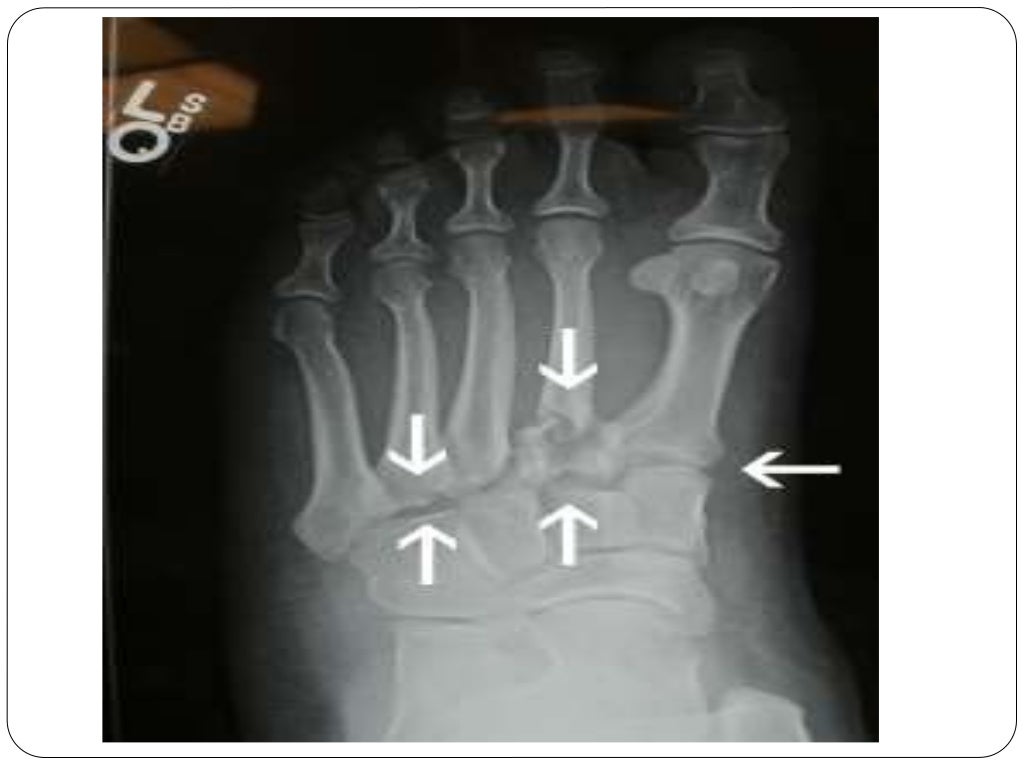

Fracture types Plaster Of Paris tecniques and Complications